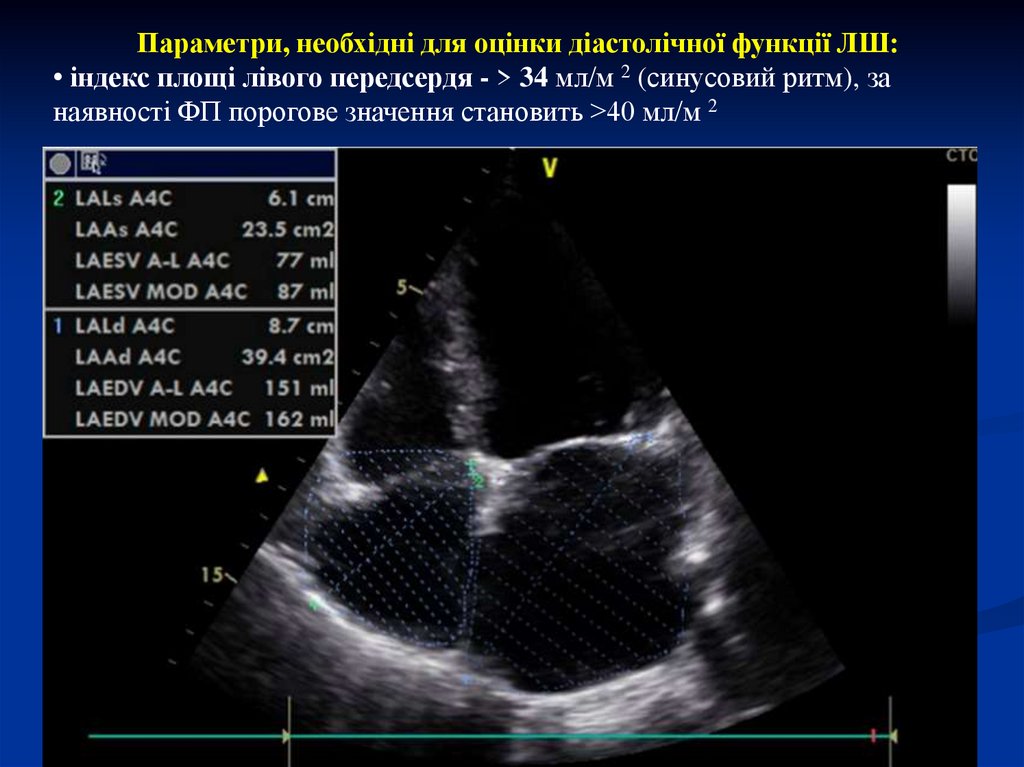

Параметри, необхідні для оцінки діастолічної функції ЛШ:

• індекс площі лівого передсердя - > 34 мл/м 2 (синусовий ритм), за

наявності ФП порогове значення становить >40 мл/м 2